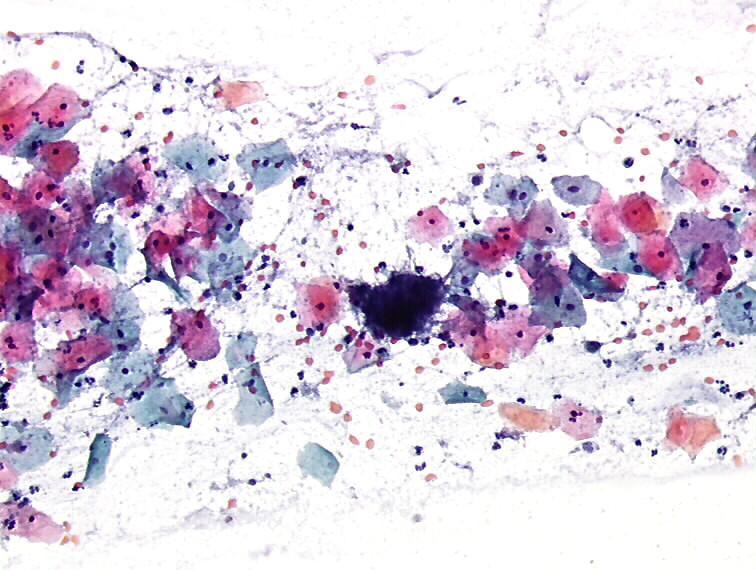

Fig. 2.51 Negative for intraepithelial lesion or malignancy (NILM). Trichomonas vaginalis What Is Abrasive Cytopathology Abrasive balloon devices are inexpensive (costing one sixth that of endoscopy and biopsy), easy to use, and provide rapid results. Overview of cytopathology procedures and techniques. Both generally focuson host (e.g. To describe a method to retrieve cellular and tissue elements of oral squamous. Abrasive cytology(artificial enhanced exfoliation) cells are obtained directly from the surface of the target of interest.. What Is Abrasive Cytopathology.